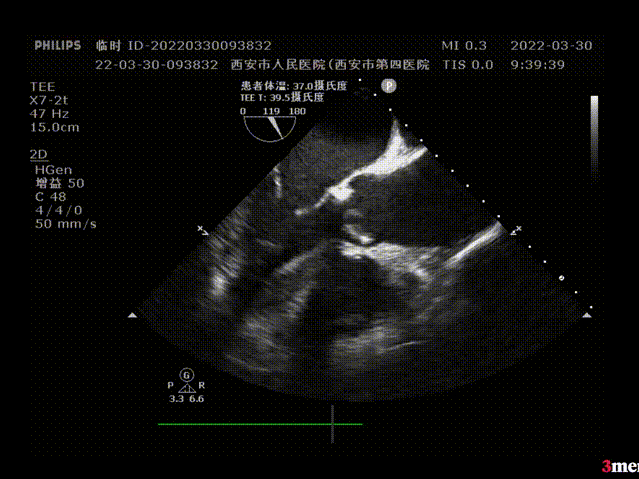

超声评估:

植入前超声评估:瓣叶开闭不良

植入后超声评估:瓣膜形态良好,无瓣周漏